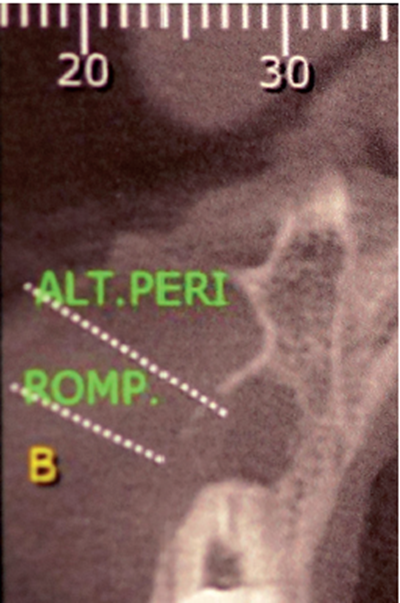

Paciente A.N., sexo feminino, 54 anos, procurou a clínica odontológica com fistula na região do elemento 11 (Figura 1). Foi solicitada tomografia computadorizada Cone Beam da região (Figura 2). Ao exame tomográfico foi diagnosticada a lesão periapical extensa, com perda óssea, envolvendo o elemento 11 (Figura 3). O plano de tratamento proposto foi a exodontia do elemento 11, curetagem da lesão e instalação imediata de um implante Cone Morse, juntamente com o procedimento de ROG, fazendo uso de biomaterial de origem bovina (Bio-Oss 0,25) e membrana de PTFE-d (Cytoplast TXT–200, Osteogenics – Lubbock TX, EUA) no mesmo momento cirúrgico.